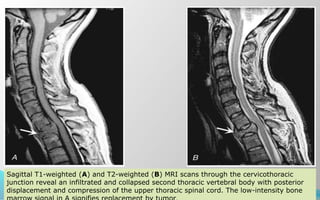

Sagittal T1-weighted (A) and T2-weighted (B) MRI scans through the cervicothoracic

junction reveal an infiltrated and collapsed second thoracic vertebral body with posterior

displacement and compression of the upper thoracic spinal cord. The low-intensity bone